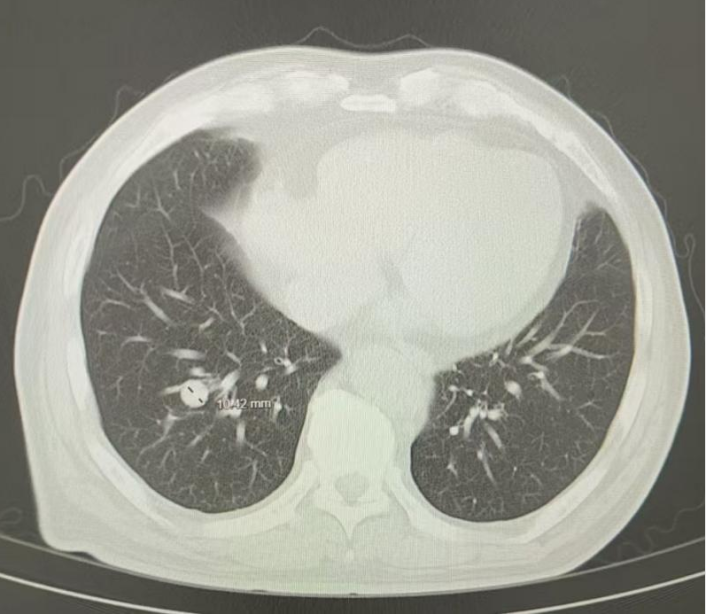

2024年6月(治疗后2个月),复查胸部CT:两肺多发结节,转移灶首拟,对比2024.4.16老片,两肺结节有所减小,疗效评估为部分缓解(PR);无明显并发症;肿瘤指标等生化检查结果良好;无明显药物副作用

图2 患者治疗后2个月胸部影像学图像(2024年6月17日)